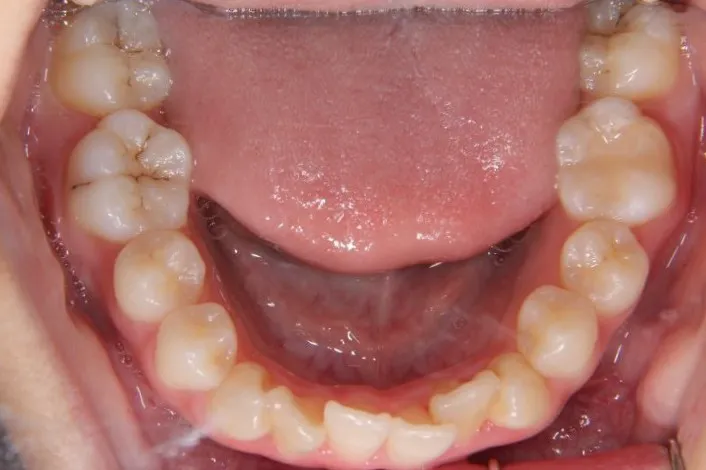

初診時年齢 高校生 (女性) 主訴 歯並びがガタガタ・口元の突出感

診断名 叢生・開咬・上下顎前突 装置名

状態 ガタガタ・でこぼこに生えている(叢生)

受け口(下顎前突/反対咬合)

前歯で噛めない(開咬/オープンバイト)

ガタガタの歯並びにお悩みの患者様でした。

口唇の突出感の他、下顎面高が長い印象も認められました。